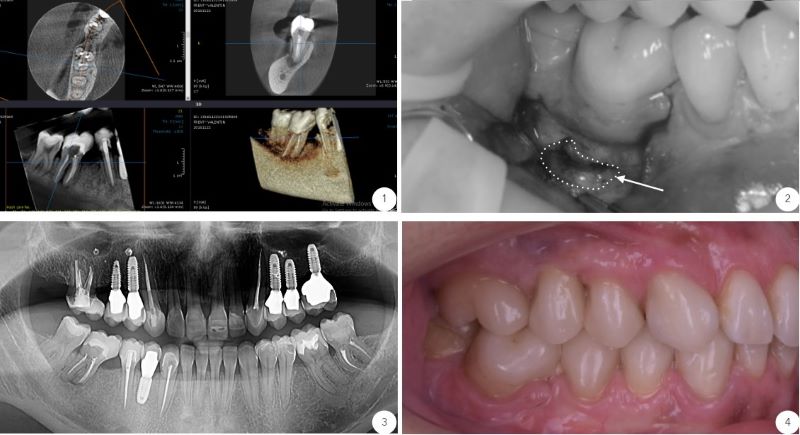

Molar cu micro-chirurgie endodontică in cazul prezentat mai sus:

1. Imagine radiologică computer tomograf inițială, evidențiază leziunea apicală (la vârful rădăcinii) molarului prim inferior dreapta. Acesta a fost tratat endodontic corect în antecedente, însă cu toate acestea leziunea nu s-a vindecat și a necesitat rezecție micro-chirurgicală;

2. Accesul la leziune s-a realizat prin defectul osos creat de aceasta. Porțiunea apicală de 3 mm din vârful rădăcinii împreună cu țesutul de granulație (țesut infectat) au fost îndepărtate, ulterior porțiunea apicală (vârful) rădăcinii fiind obturat cu un material specific (procedură asemănătoare cu cea de obturare - plombare), însă la vărful rădăcinii;

3. Imaginea radiologică computer tomograf de control evidențiază vindecarea țesutului osos din jurul rădăcinii molarului la 6 luni de la intervenție;

4. Aspectul clinic la 1 an de la intervenție arată o gingie sănătoasă cu aspect normal.